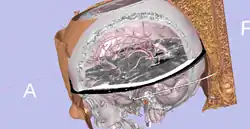

Hardware accelerated volume rendering with OpenGL.

Hardware accelerated volume rendering with OpenGL. -